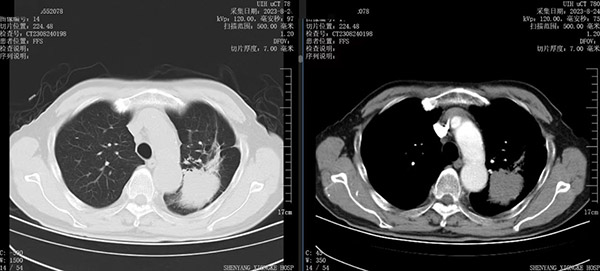

综合患者的状况,首选治疗方案是使用肺癌靶向药物,根据基因检测结果EGFR19外显子缺失突变,丰度1.5%,给予阿法替尼靶向治疗。口服靶向药期间,患者定期复查,一年半后逐渐出现咳嗽、喘息气短,复查肺CT发现左肺上叶病灶增大,同时出现左侧胸膜转移,左肾上腺转移。根据肿瘤进展情况,应更换靶向药物及静脉化疗,不过家属及刘大爷都拒绝进行化疗。根据肿瘤的分期、阶段,再结合患者身体状况,介入科团队拟采用放射性粒子植入术,以控制肿瘤的进展,家属及患者在详细了解方案后对粒子植入的疗法也非常认可。经过充分的术前讨论及准备,手术如期开展,术中按照预先拟定好的TPS计划系统均匀布放43颗粒子,仅30分钟成功实施粒子植入术。术后半个月刘大爷的咳嗽明显减轻,左肺病灶从83X49mm明显缩小到58X21mm。粒子植入术后至今,患者状态一直良好。

放射性粒子植入术后1个月复查左肺病灶从83*49mm缩小到58*21mm,疗效CR